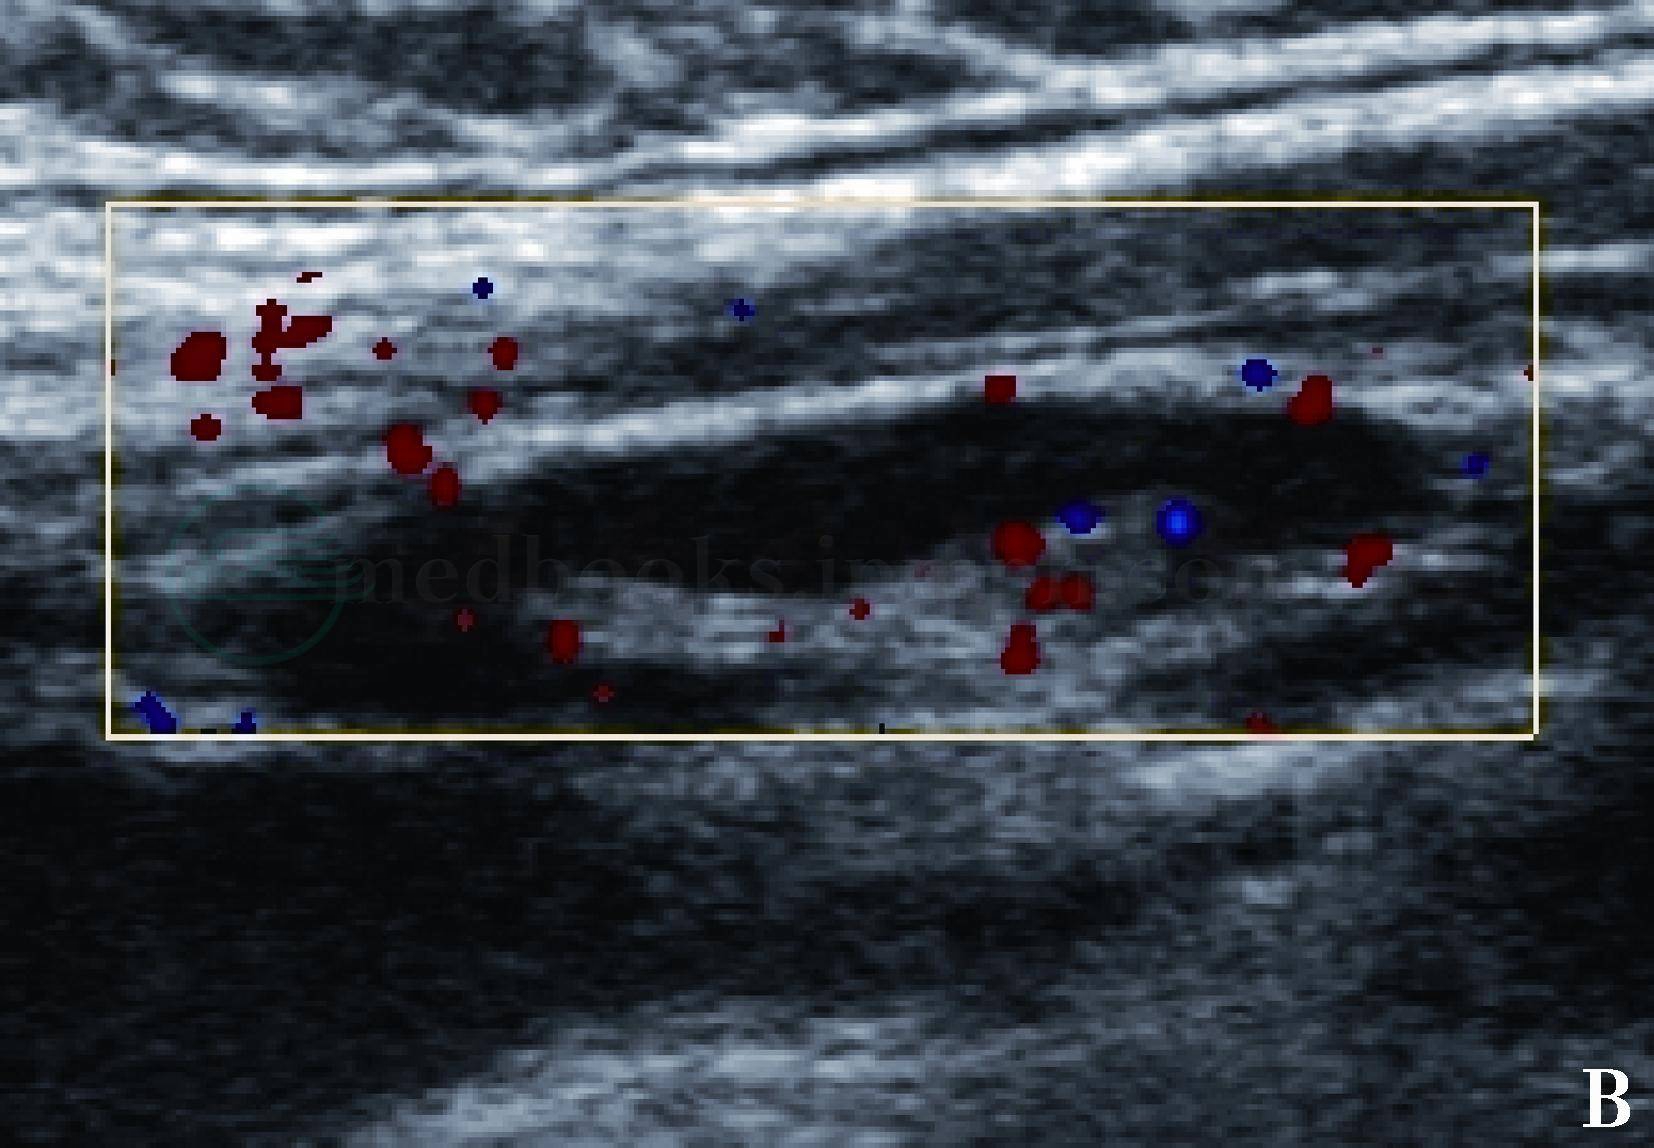

图4 正常腹股沟淋巴结声像图

彩色多普勒超声显示淋巴结髓质内短条状血流